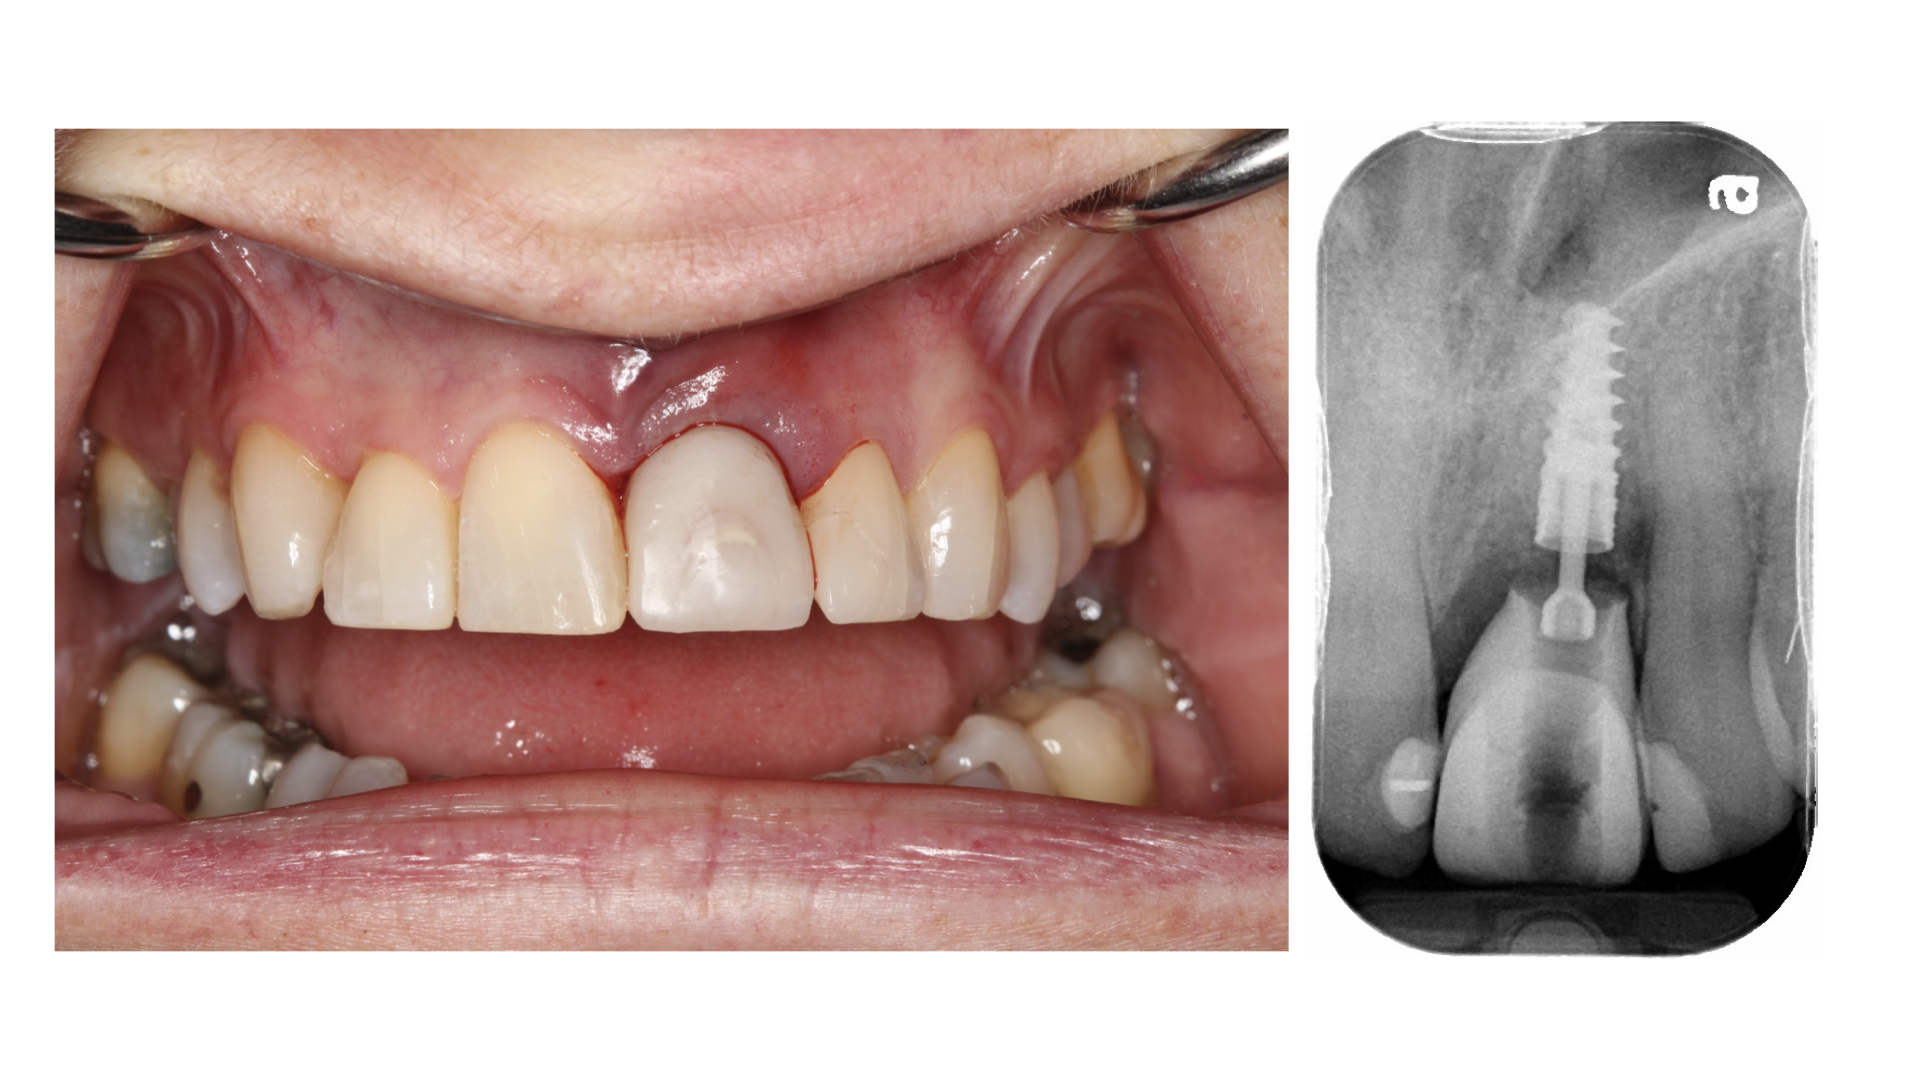

Prosthetically Driven Implant Surgery: Redefined

OH-Powell-main alternate text for this image

Introduction Looking at online forums that discuss dental implants, one cannot help but notice a heavy emphasis on the surgical aspect of implant prosthodontics with the prosthodontic phase often overlooked or barely discussed. It is our opinion that this line of thinking often results in multiple (sometimes unnecessary) surgical procedures that may yield outcomes that … Read more